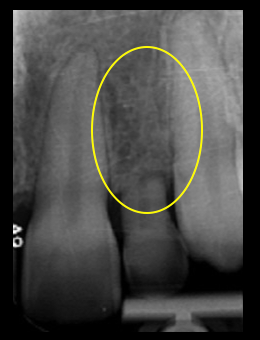

Additionally, the guide must be used for diagnostic radiology by casting a shadow on the X-ray film of the guide’s relationship with the underlying bone. The key feature of the surgical guide is the designation of the implant’s apico-coronal, mesio-distal, and oro-facial positioning. Much information is transferred from these surgical guides to the implant surgeon.

Implant depth is crucial for adequate “running room” and emergence profile. Ideally, the implant should be placed 3 mm apical to the gingival extent of the proposed restoration. Placing implants too shallow creates emergence contour limitations that create unesthetic gingival scallops. If the implant is placed too deeply, the tissue support and papilla formation may be compromised.

Tarnow has shown that if the distance of the implant platform and gingival tissue is greater than 5.0 mm, the interproximal papilla will be created less than 50% of the time. These surgical guides provide an unobtrusive visualization of the restoration margin and the implant platform at the time of placement.